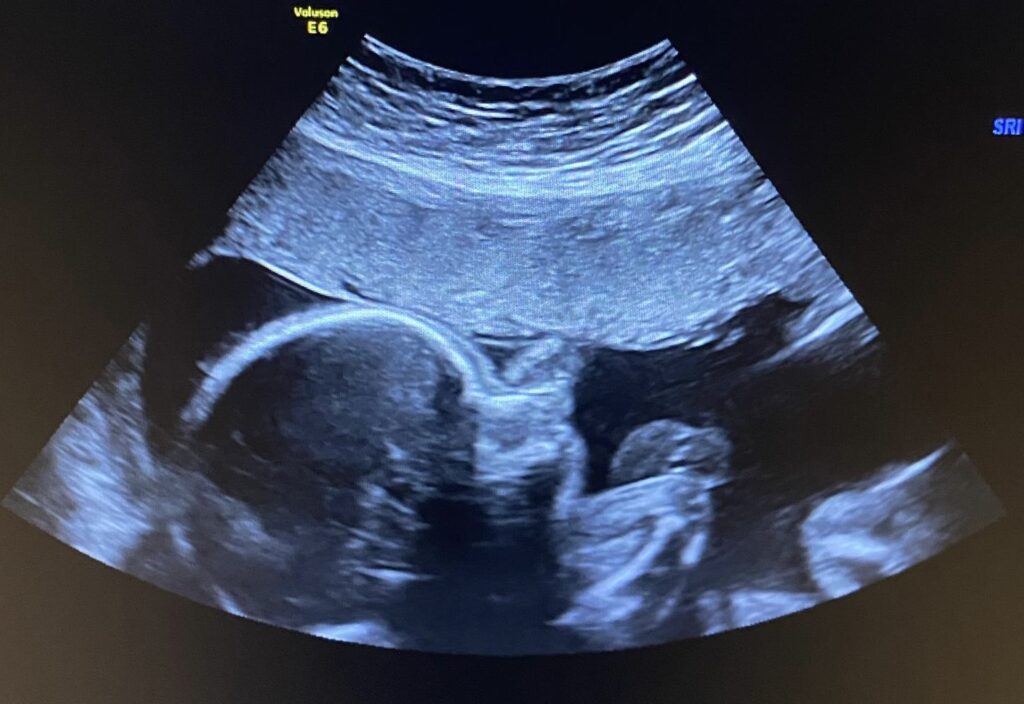

Vanuit Zambia wensen we iedereen een gezond en voorspoedig 2026! Traditiegetrouw hoort daar een gezinsfoto bij, vers van de pers. Deze keer bevat die voor velen van jullie een kleine, of eigenlijk grote, verrassing: een dikke buik! 😄

Begin april verwachten we gezinsuitbreiding. Wat een feest! Dit kindje is nu al zó geliefd en zó welkom. We geloven dat 2026 een jaar zal zijn van uitbreiding en groei. Dat zal niet altijd makkelijk zijn en soms zelfs pijnlijk (zo ben ik na tien jaar écht vergeten hoe weeën voelen!), maar we blijven op God zien, op de bergen én in de dalen. Hij heeft ons al zo ver gebracht; dat vervult ons met dankbaarheid en vertrouwen voor de toekomst. En diezelfde hoop en dat vertrouwen wensen we jullie toe voor het nieuwe jaar, temidden van de chaos en pijn in deze wereld, soms ver weg, maar soms ook ook heel dichtbij.

Yaelle, Eloise, David en het dametje op onderstaande foto 🙂